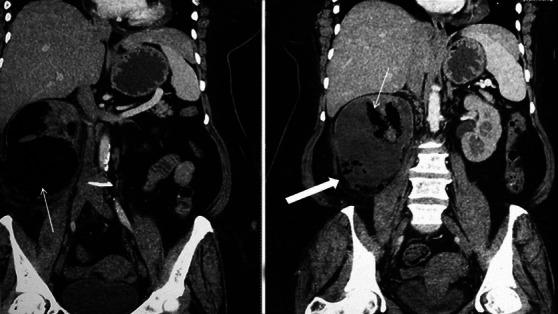

We present our experience of 22 cases of emphysematous pyelonephritis (EPN) treated from 1996 to 2012. Medical records were analyzed retrospectively for demographic profile, presence and duration of diabetes mellitus, and mode of clinical presentation. EPN was diagnosed based on demonstration of intra-renal gas by plain X-ray, ultrasound, and/or computed tomography (CT) scan. Details of medical treatment, reason for surgical intervention, and final outcome were recorded. Univariate analysis was performed to identify risk factors for mortality and P value of less than 0.05 was taken as significant. Twenty-two cases (6 males, 16 females) of EPN were diagnosed. Seven cases presented with acute pyelonephritis, seven cases with urosepsis, and the remaining eight patients with multi-organ dysfunction. CT grading of EPN was class IV in three, class III in four, class II in 14, and class I in one. All were initially managed medically with parenteral antibiotics. Ten patients needed additional surgical intervention. The overall survival rate was 86.3% (19/22). Among the risk factors analyzed higher CT grade, altered sensorium and thrombocytopenia were significantly associated with mortality. We conclude that a more conservative approach in managing EPN has become the standard of care. Patients having high CT grade of lesions (III and IV) with altered sensorium and thrombocytopenia at presentation are more likely to die due to the disease and may be better managed by an aggressive surgical plan.